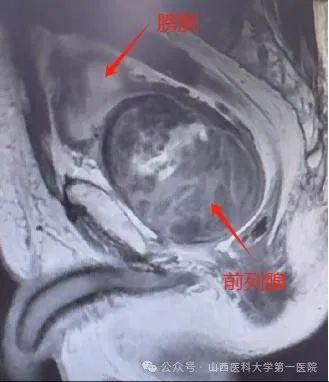

患者为76岁老年男性,进行性排尿困难5年余,半月前出现严重血尿,就诊于外院,给予抗休克、输血等对症治疗后,经尿道内腔镜下探查,考虑前列腺挤压出血,建议上级医院进一步诊治,遂来山医大一院就诊。患者入院后完善前列腺核磁,提示前列腺体积约8.1cm*7.9cm*9.2cm,约306cm³,属于极重度前列腺增生,是普通人前列腺的十几倍。经过全科室讨论后,考虑患者既往高血压、糖尿病、心脏病、脑梗等病史,前列腺体积巨大,经尿道手术空间狭小,操作难度大,手术时间长,决定行机器人腹腔镜前列腺切除术,术中视野更大,操作更精细,出血更少,同时经膀胱入路能最大程度保护患者尿控,使患者更受益。